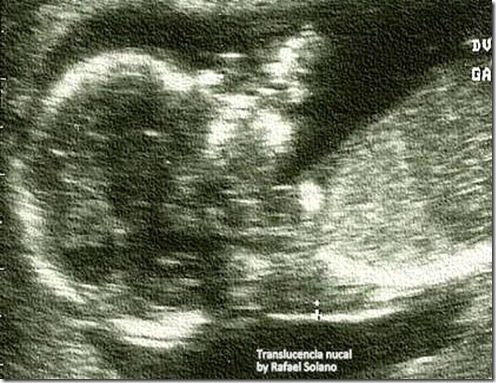

¿Qué es la Translucencia Nucal?

Durante las semanas 11-14 del embarazo se pueden realizar estudios de detección para anormalidades cromosómicas (por ejemplo, síndrome de Down). Estos consisten en la medición de la translucencia nucal, combinada con marcadores en sangre y todo ello ajustado por la edad materna.

La translucencia nucal es un espacio situado en la parte posterior de la nuca del feto, la cual es medida a través de un ultrasonido abdominal. Ésta, se encuentra asociada a mayor riesgo para anormalidades cromosómicas cuando su grosor supera los 3.5 mm. Además, no solo se asocia con cromosomopatías, también está asociada a otras anomalías (como anormalidades cardiacas).